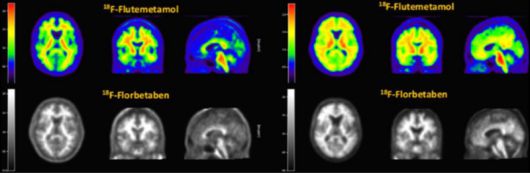

알츠하이머 치매 진단을 위해 쓰이는 '비자밀'(윗쪽 컬러 사진)과 '뉴라체크'(아랫쪽 흑백 사진) PET-CT 영상 비교 (자료=듀켐바이오) |